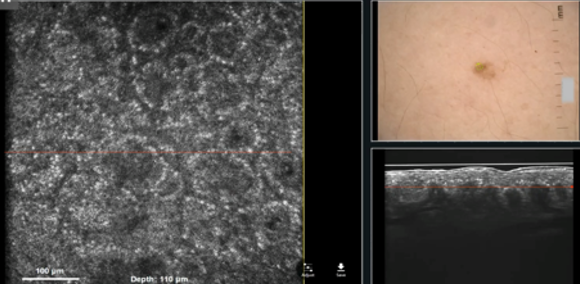

Click to view moreLeading imaging technologies advancing non-invasive dermatological diagnostics